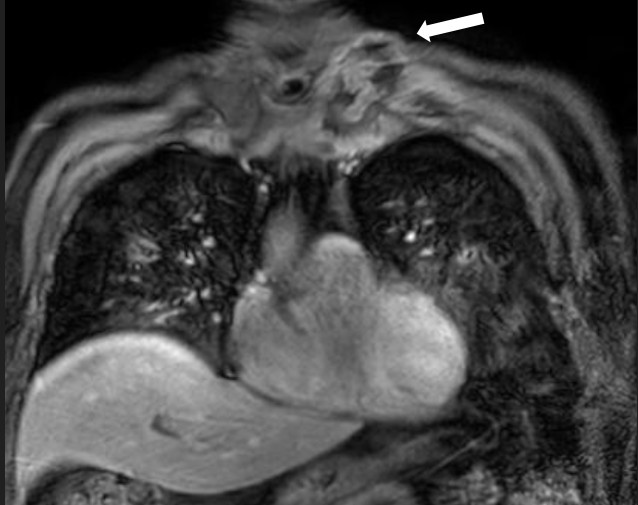

MRI of the chest showed findings consistent with osteomyelitis, including bone irregularities, edema, subchondral erosions of the right sternoclavicular joint, synovitis, and inflammatory joint changes (Fig. 2- 4).

Figure 2. Sagittal magnetic resonance imaging (POS-DIXON) (Multi-Dixon). Lytic lesion with ill-defined contour and soft tissue edema (stenoclavicular)